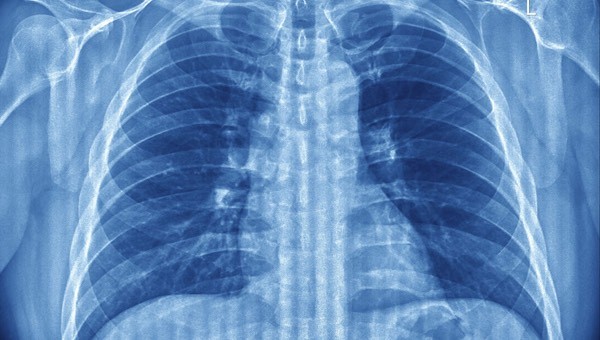

Nefes darlığı birçok nedene bağlı bir şekilde meydana çıkabilir. Bu sebeple alanında uzman bir doktora danışmak önemlidir. Nefes darlığı neden olur sorusu da bu sebeple sık sık araştırılan konular arasında yer alır. Fiziksel ve psikolojik nedenler bağlı olarak gelişebilen nefes darlığının tedavisi altta yatan soruna göre oluşturulur. Nefes darlığı neden olur sorusu için şu cevaplar verilebilir;

- Solunum yolu hastalıkları

- Akciğer sönmesi